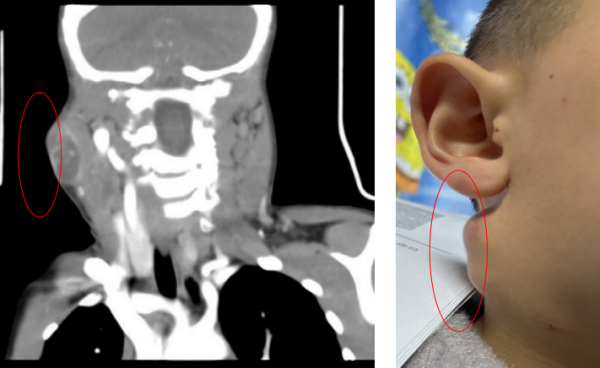

入院后,学生儿童结核科副主任周海依为孩子进行了仔细的检查,发现孩子颈部有多发淋巴结肿大,右下颌处有一直径约3CM的包块,表面红肿破溃,按压有波动感;左侧有三个包块,最大的直径为2.5CM左右。经过进一步完善检查,认为结核病诊断依据不足,联合耳鼻咽喉头颈外科副主任、主任医师周定刚会诊,明确有手术指征,转耳鼻咽喉头颈外科,完善术前准备后行双侧颌下淋巴结清扫术+皮瓣修整术。

术后耳鼻咽喉头颈外科将病变淋巴结组织送检,同时行宏基因测序,未找到结核杆菌,排除了淋巴结核的可能,提示高通量的汉赛巴尔通体。经过MDT专家团队会诊讨论,了解到孩子暑假期间曾有被家里宠物猫咪抓伤病史,而汉赛巴尔通体恰好就是寄居于猫科动物上的一种人兽共患致病菌,由此,推断出孩子患上了“猫抓病”。明确病因后,MDT团队调整治疗方案给予针对性用药,孩子病情好转出院。出院后医生进行了电话回访,得知孩子目前康复情况良好,肿大的淋巴结已基本消退。

术前术后对比图